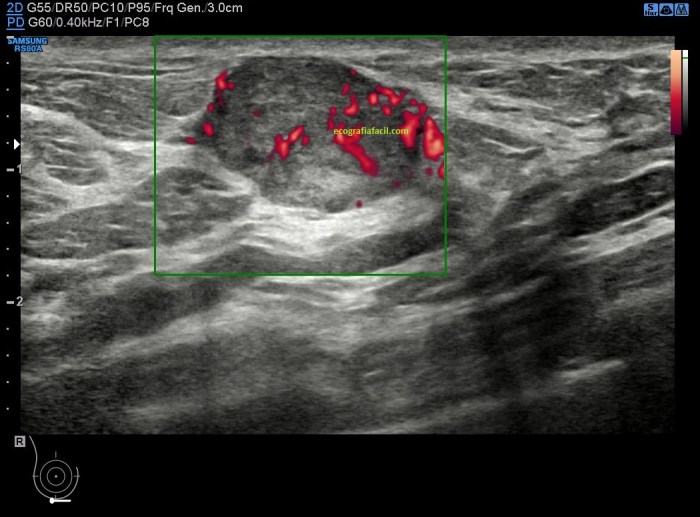

Si el seroma se infectase tendríamos un absceso o colección, normalmente purulenta, que en ocasiones puede requerir la colocación de un drenaje como ves en las dos imágenes siguientes.

El absceso suele ser hipoecogénico.

En la imagen siguiente puedes observar los tubos de drenaje en forma ecográfica de «cuerpo extraño», tubular, hiperecogénico, dentro del absceso.